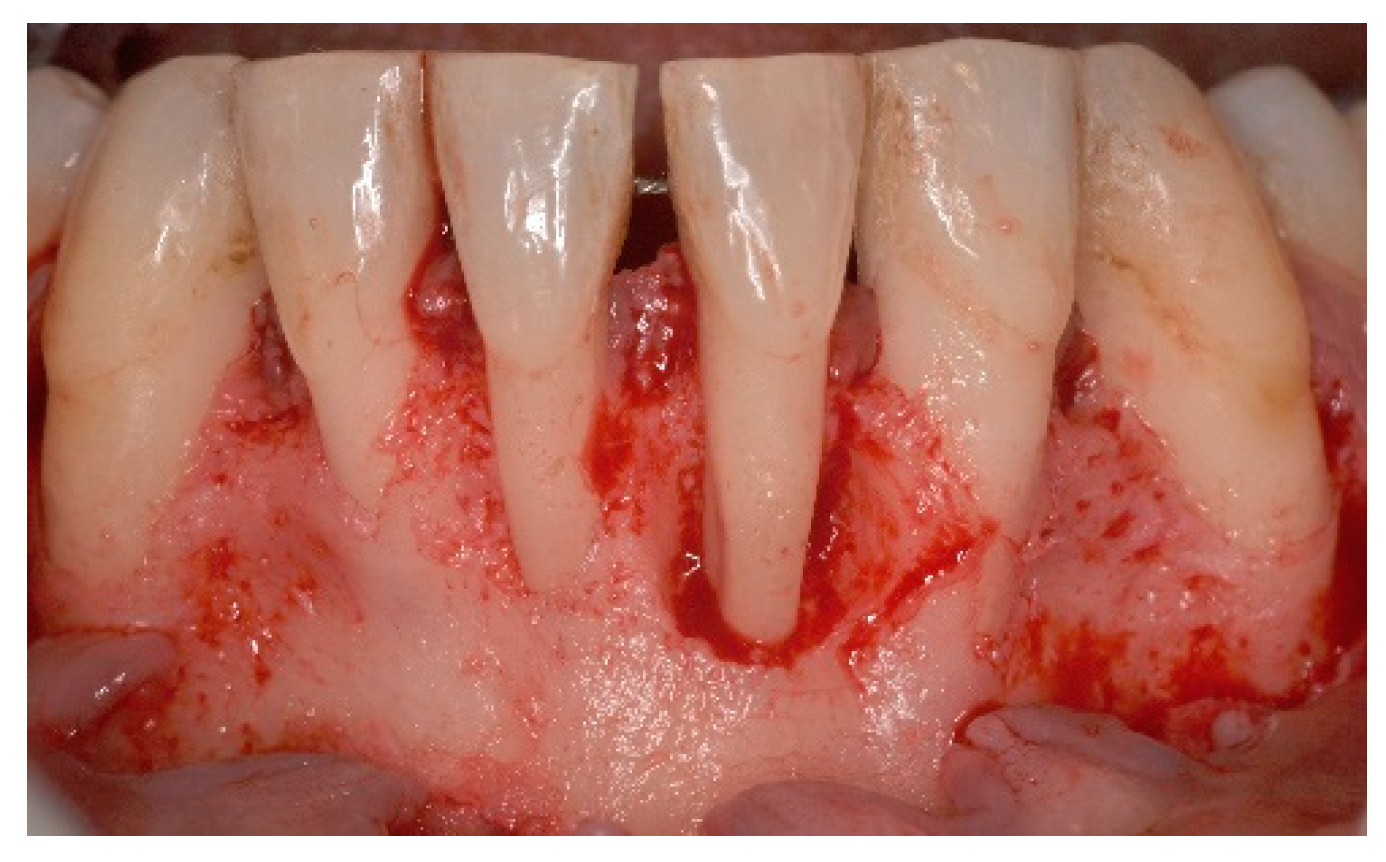

4. Free Connective Tissue Grafts in Periodontal Regenerative Procedures

5. Materials and Methods